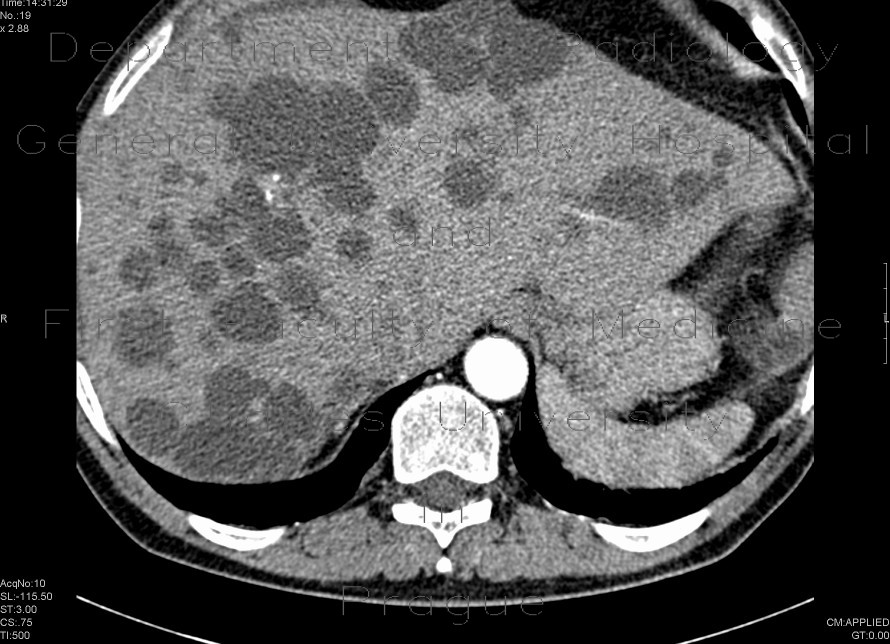

Mutliple bilateral cyst replacing parenchyma, both kidneys are enlarged. Multiple cysts in liver.

Radiology image - Polycystosis of kidney and liver: Abdomen, Kidney and adrenals, Liver: CT - Computed tomography